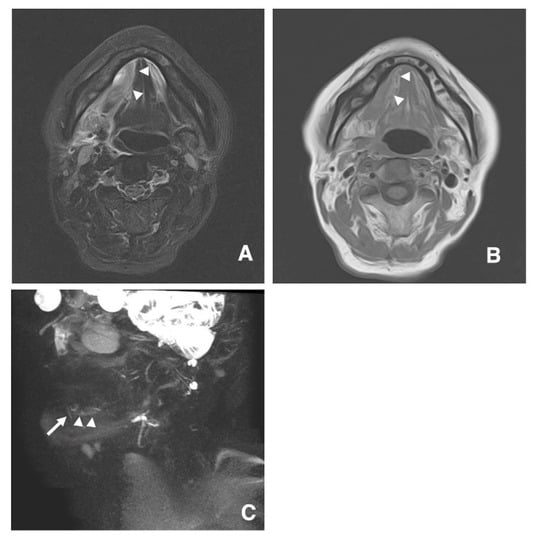

3.1. Visualization of Sublingual Gland Ducts by MR Sialography

3.2. Function of Sublingual Gland Ducts Evaluated by Dynamic MR Sialography

3.3. Clinical Application of MR Sialography for Patients with Sublingual Gland Diseases